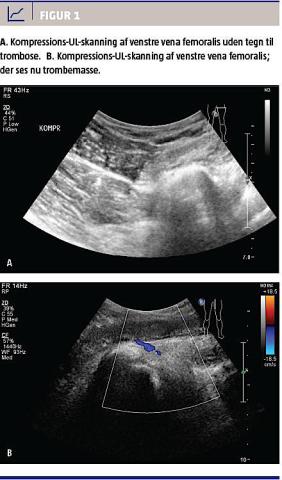

29 mg/l (referenceværdi: < 10 mg/l). Patienten var afebril, der var normalt resultat af elektrokardiogram og upåfaldende arteriegasanalyse. En UL-skanning samme dag viste ikke tegn til trombose i vena poplitea eller v. femoralis (Figur 1A).

Patienten blev sendt hjem, men genhenvist tre dage senere pga. forværring af symptomerne med tiltagende smerter i lænden og lysken. Ved en objektiv undersøgelse blev der fundet hævelse af hele venstre underekstremitet til lyskeniveau og rødme/varme ved de dybe vener på femur. UL-skanning af venstre underekstremitet og nedre abdomen blev gentaget, og her blev der påvist trombose af v. poplitea, v. femoralis, v. iliaca externa og communis til v. cava inferior, som ikke var inddraget (Figur 1B).